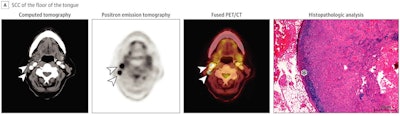

Images of a 71-year-old woman with SCC of the floor of the tongue. Although the CT image is rather unremarkable, PET depicted intense focal tracer uptake in two cervical lymph nodes (arrowheads), which is highly consistent with metastatic disease. PET findings could be confirmed by histopathologic analysis with the presence of a keratinizing, moderately to poorly differentiated SCC. Only a small rim of retained lymph node tissue could be identified (star) and most of the lymph node was occupied by carcinoma. All images courtesy of JAMA Network Open.